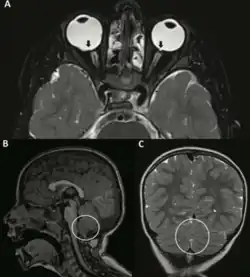

MR brain findings in a person with Beck–Fahrner syndrome: A. bilateral coloboma; B. underdeveloped inferior cerebellar vermis; C. mildly abnormal midline cerebellum surface.

Decreased tone of muscles is most noticeable in early life, causing feeding difficulties and constipation in infants, and further impeding the development of speech and motor skills in children. Epilepsy and seizure disorders affect over one-third of individuals, while some individuals encounter motor and movement disorders. Eye involvement can lead to vision, movement and alignment issues, and ear involvement may result in hearing loss. Affected individuals may at times demonstrate benign brain malformations in neuroimaging studies.[4]